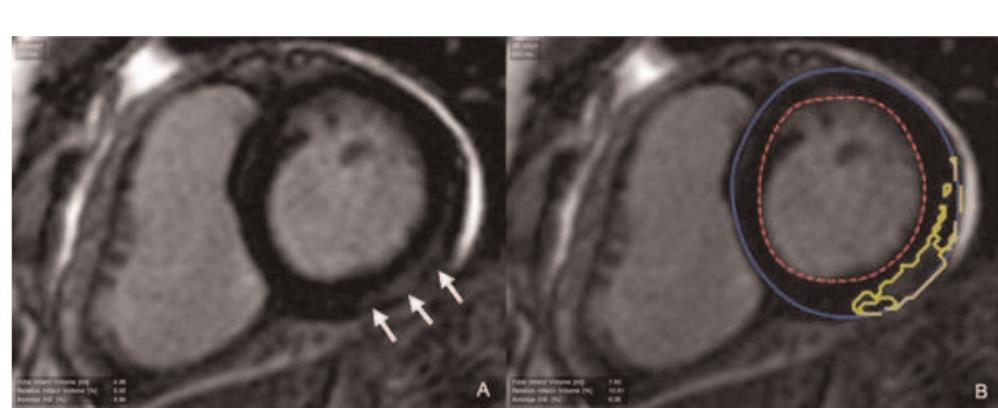

Introduction: Prophylactic implantation of a cardioverter/ defibrillator (ICD) has been shown to reduce mortality in patients with chronic myocardial infarction (CMI) and an increased risk for life threatening ventricular arrhythmia (VA). The use of ICDs in this large patient population is still limited by high costs and possible adverse events including inappropriate discharges and progression of heart failure. VA is related to infarct size and seems to be related to infarct morphology. Contrast enhanced cardiovascular magnetic resonance imaging (ceCMR) can detect and quantify myocardial fibrosis in the setting of CMI and might therefore be a valuable tool for a more accurate risk stratification in this setting. Hypothesis: ceCMR can identify the subgroup developing VA in patients with prophylactic ICD implantation following MADIT criteria. Methods: We prospectively enrolled 52 patients (49 males, age 69 ± 10 years) with CMI and clinical indication for ICD therapy following MADIT criteria. Prior to implantation (36 ± 78 days) patients were investigated on a 1.5 T clinical scanner (Siemens Avanto © , Germany) to assess left ventricular function (LVEF), LV end-diastolic volume (LVEDV) and LV mass (sequence parameters: GRE SSFP, matrix 256 × 192, short axis stack; full LV coverage, no gap; slice thickness 6 mm). For quantitative assessment of infarct morphology late gadolinium enhancement (LGE) was performed including measurement of total and relative infarct mass (related to LV mass) and the degree of transmurality (DT) as defined by the percentage of transmurality in each scar. (sequence parameters: inversion recovery gradient echo; matrix 256 × 148, imaging 10 min after 0.2 μg/kg gadolinium DTPA; slice orientation equal to SSFP). MRI images were analysed using dedicated software (MASS © , Medis,

Introduction: Prophylactic implantation of a cardioverter/ defibrillator (ICD) has been shown to reduce mortality in patients with chronic myocardial infarction (CMI) and an increased risk for life threatening ventricular arrhythmia (VA). The use of ICDs in this large patient population is still limited by high costs and possible adverse events including inappropriate discharges and progression of heart failure. VA is related to infarct size and seems to be related to infarct morphology. Contrast enhanced cardiovascular magnetic resonance imaging (ceCMR) can detect and quantify myocardial fibrosis in the setting of CMI and might therefore be a valuable tool for a more accurate risk stratification in this setting. Hypothesis: ceCMR can identify the subgroup developing VA in patients with prophylactic ICD implantation following MADIT criteria. Methods: We prospectively enrolled 52 patients (49 males, age 69 ± 10 years) with CMI and clinical indication for ICD therapy following MADIT criteria. Prior to implantation (36 ± 78 days) patients were investigated on a 1.5 T clinical scanner (Siemens Avanto © , Germany) to assess left ventricular function (LVEF), LV end-diastolic volume (LVEDV) and LV mass (sequence parameters: GRE SSFP, matrix 256 × 192, short axis stack; full LV coverage, no gap; slice thickness 6 mm). For quantitative assessment of infarct morphology late gadolinium enhancement (LGE) was performed including measurement of total and relative infarct mass (related to LV mass) and the degree of transmurality (DT) as defined by the percentage of transmurality in each scar. (sequence parameters: inversion recovery gradient echo; matrix 256 × 148, imaging 10 min after 0.2 μg/kg gadolinium DTPA; slice orientation equal to SSFP). MRI images were analysed using dedicated software (MASS © , Medis,

Introduction: Prophylactic implantation of a cardioverter/ defibrillator (ICD) has been shown to reduce mortality in patients with chronic myocardial infarction (CMI) and an increased risk for life threatening ventricular arrhythmia (VA). The use of ICDs in this large patient population is still limited by high costs and possible adverse events including inappropriate discharges and progression of heart failure. VA is related to infarct size and seems to be related to infarct morphology. Contrast enhanced cardiovascular magnetic resonance imaging (ceCMR) can detect and quantify myocardial fibrosis in the setting of CMI and might therefore be a valuable tool for a more accurate risk stratification in this setting. Hypothesis: ceCMR can identify the subgroup developing VA in patients with prophylactic ICD implantation following MADIT criteria. Methods: We prospectively enrolled 52 patients (49 males, age 69 ± 10 years) with CMI and clinical indication for ICD therapy following MADIT criteria. Prior to implantation (36 ± 78 days) patients were investigated on a 1.5 T clinical scanner (Siemens Avanto © , Germany) to assess left ventricular function (LVEF), LV end-diastolic volume (LVEDV) and LV mass (sequence parameters: GRE SSFP, matrix 256 × 192, short axis stack; full LV coverage, no gap; slice thickness 6 mm). For quantitative assessment of infarct morphology late gadolinium enhancement (LGE) was performed including measurement of total and relative infarct mass (related to LV mass) and the degree of transmurality (DT) as defined by the percentage of transmurality in each scar. (sequence parameters: inversion recovery gradient echo; matrix 256 × 148, imaging 10 min after 0.2 μg/kg gadolinium DTPA; slice orientation equal to SSFP). MRI images were analysed using dedicated software (MASS © , Medis,

Introduction: Prophylactic implantation of a cardioverter/ defibrillator (ICD) has been shown to reduce mortality in patients with chronic myocardial infarction (CMI) and an increased risk for life threatening ventricular arrhythmia (VA). The use of ICDs in this large patient population is still limited by high costs and possible adverse events including inappropriate discharges and progression of heart failure. VA is related to infarct size and seems to be related to infarct morphology. Contrast enhanced cardiovascular magnetic resonance imaging (ceCMR) can detect and quantify myocardial fibrosis in the setting of CMI and might therefore be a valuable tool for a more accurate risk stratification in this setting. Hypothesis: ceCMR can identify the subgroup developing VA in patients with prophylactic ICD implantation following MADIT criteria. Methods: We prospectively enrolled 52 patients (49 males, age 69 ± 10 years) with CMI and clinical indication for ICD therapy following MADIT criteria. Prior to implantation (36 ± 78 days) patients were investigated on a 1.5 T clinical scanner (Siemens Avanto © , Germany) to assess left ventricular function (LVEF), LV end-diastolic volume (LVEDV) and LV mass (sequence parameters: GRE SSFP, matrix 256 × 192, short axis stack; full LV coverage, no gap; slice thickness 6 mm). For quantitative assessment of infarct morphology late gadolinium enhancement (LGE) was performed including measurement of total and relative infarct mass (related to LV mass) and the degree of transmurality (DT) as defined by the percentage of transmurality in each scar. (sequence parameters: inversion recovery gradient echo; matrix 256 × 148, imaging 10 min after 0.2 μg/kg gadolinium DTPA; slice orientation equal to SSFP). MRI images were analysed using dedicated software (MASS © , Medis,

Introduction: Prophylactic implantation of a cardioverter/ defibrillator (ICD) has been shown to reduce mortality in patients with chronic myocardial infarction (CMI) and an increased risk for life threatening ventricular arrhythmia (VA). The use of ICDs in this large patient population is still limited by high costs and possible adverse events including inappropriate discharges and progression of heart failure. VA is related to infarct size and seems to be related to infarct morphology. Contrast enhanced cardiovascular magnetic resonance imaging (ceCMR) can detect and quantify myocardial fibrosis in the setting of CMI and might therefore be a valuable tool for a more accurate risk stratification in this setting. Hypothesis: ceCMR can identify the subgroup developing VA in patients with prophylactic ICD implantation following MADIT criteria. Methods: We prospectively enrolled 52 patients (49 males, age 69 ± 10 years) with CMI and clinical indication for ICD therapy following MADIT criteria. Prior to implantation (36 ± 78 days) patients were investigated on a 1.5 T clinical scanner (Siemens Avanto © , Germany) to assess left ventricular function (LVEF), LV end-diastolic volume (LVEDV) and LV mass (sequence parameters: GRE SSFP, matrix 256 × 192, short axis stack; full LV coverage, no gap; slice thickness 6 mm). For quantitative assessment of infarct morphology late gadolinium enhancement (LGE) was performed including measurement of total and relative infarct mass (related to LV mass) and the degree of transmurality (DT) as defined by the percentage of transmurality in each scar. (sequence parameters: inversion recovery gradient echo; matrix 256 × 148, imaging 10 min after 0.2 μg/kg gadolinium DTPA; slice orientation equal to SSFP). MRI images were analysed using dedicated software (MASS © , Medis,

Introduction: Prophylactic implantation of a cardioverter/ defibrillator (ICD) has been shown to reduce mortality in patients with chronic myocardial infarction (CMI) and an increased risk for life threatening ventricular arrhythmia (VA). The use of ICDs in this large patient population is still limited by high costs and possible adverse events including inappropriate discharges and progression of heart failure. VA is related to infarct size and seems to be related to infarct morphology. Contrast enhanced cardiovascular magnetic resonance imaging (ceCMR) can detect and quantify myocardial fibrosis in the setting of CMI and might therefore be a valuable tool for a more accurate risk stratification in this setting. Hypothesis: ceCMR can identify the subgroup developing VA in patients with prophylactic ICD implantation following MADIT criteria. Methods: We prospectively enrolled 52 patients (49 males, age 69 ± 10 years) with CMI and clinical indication for ICD therapy following MADIT criteria. Prior to implantation (36 ± 78 days) patients were investigated on a 1.5 T clinical scanner (Siemens Avanto © , Germany) to assess left ventricular function (LVEF), LV end-diastolic volume (LVEDV) and LV mass (sequence parameters: GRE SSFP, matrix 256 × 192, short axis stack; full LV coverage, no gap; slice thickness 6 mm). For quantitative assessment of infarct morphology late gadolinium enhancement (LGE) was performed including measurement of total and relative infarct mass (related to LV mass) and the degree of transmurality (DT) as defined by the percentage of transmurality in each scar. (sequence parameters: inversion recovery gradient echo; matrix 256 × 148, imaging 10 min after 0.2 μg/kg gadolinium DTPA; slice orientation equal to SSFP). MRI images were analysed using dedicated software (MASS © , Medis,

Introduction: Prophylactic implantation of a cardioverter/ defibrillator (ICD) has been shown to reduce mortality in patients with chronic myocardial infarction (CMI) and an increased risk for life threatening ventricular arrhythmia (VA). The use of ICDs in this large patient population is still limited by high costs and possible adverse events including inappropriate discharges and progression of heart failure. VA is related to infarct size and seems to be related to infarct morphology. Contrast enhanced cardiovascular magnetic resonance imaging (ceCMR) can detect and quantify myocardial fibrosis in the setting of CMI and might therefore be a valuable tool for a more accurate risk stratification in this setting. Hypothesis: ceCMR can identify the subgroup developing VA in patients with prophylactic ICD implantation following MADIT criteria. Methods: We prospectively enrolled 52 patients (49 males, age 69 ± 10 years) with CMI and clinical indication for ICD therapy following MADIT criteria. Prior to implantation (36 ± 78 days) patients were investigated on a 1.5 T clinical scanner (Siemens Avanto © , Germany) to assess left ventricular function (LVEF), LV end-diastolic volume (LVEDV) and LV mass (sequence parameters: GRE SSFP, matrix 256 × 192, short axis stack; full LV coverage, no gap; slice thickness 6 mm). For quantitative assessment of infarct morphology late gadolinium enhancement (LGE) was performed including measurement of total and relative infarct mass (related to LV mass) and the degree of transmurality (DT) as defined by the percentage of transmurality in each scar. (sequence parameters: inversion recovery gradient echo; matrix 256 × 148, imaging 10 min after 0.2 μg/kg gadolinium DTPA; slice orientation equal to SSFP). MRI images were analysed using dedicated software (MASS © , Medis,

Introduction: Prophylactic implantation of a cardioverter/ defibrillator (ICD) has been shown to reduce mortality in patients with chronic myocardial infarction (CMI) and an increased risk for life threatening ventricular arrhythmia (VA). The use of ICDs in this large patient population is still limited by high costs and possible adverse events including inappropriate discharges and progression of heart failure. VA is related to infarct size and seems to be related to infarct morphology. Contrast enhanced cardiovascular magnetic resonance imaging (ceCMR) can detect and quantify myocardial fibrosis in the setting of CMI and might therefore be a valuable tool for a more accurate risk stratification in this setting. Hypothesis: ceCMR can identify the subgroup developing VA in patients with prophylactic ICD implantation following MADIT criteria. Methods: We prospectively enrolled 52 patients (49 males, age 69 ± 10 years) with CMI and clinical indication for ICD therapy following MADIT criteria. Prior to implantation (36 ± 78 days) patients were investigated on a 1.5 T clinical scanner (Siemens Avanto © , Germany) to assess left ventricular function (LVEF), LV end-diastolic volume (LVEDV) and LV mass (sequence parameters: GRE SSFP, matrix 256 × 192, short axis stack; full LV coverage, no gap; slice thickness 6 mm). For quantitative assessment of infarct morphology late gadolinium enhancement (LGE) was performed including measurement of total and relative infarct mass (related to LV mass) and the degree of transmurality (DT) as defined by the percentage of transmurality in each scar. (sequence parameters: inversion recovery gradient echo; matrix 256 × 148, imaging 10 min after 0.2 μg/kg gadolinium DTPA; slice orientation equal to SSFP). MRI images were analysed using dedicated software (MASS © , Medis,

Introduction: Prophylactic implantation of a cardioverter/ defibrillator (ICD) has been shown to reduce mortality in patients with chronic myocardial infarction (CMI) and an increased risk for life threatening ventricular arrhythmia (VA). The use of ICDs in this large patient population is still limited by high costs and possible adverse events including inappropriate discharges and progression of heart failure. VA is related to infarct size and seems to be related to infarct morphology. Contrast enhanced cardiovascular magnetic resonance imaging (ceCMR) can detect and quantify myocardial fibrosis in the setting of CMI and might therefore be a valuable tool for a more accurate risk stratification in this setting. Hypothesis: ceCMR can identify the subgroup developing VA in patients with prophylactic ICD implantation following MADIT criteria. Methods: We prospectively enrolled 52 patients (49 males, age 69 ± 10 years) with CMI and clinical indication for ICD therapy following MADIT criteria. Prior to implantation (36 ± 78 days) patients were investigated on a 1.5 T clinical scanner (Siemens Avanto © , Germany) to assess left ventricular function (LVEF), LV end-diastolic volume (LVEDV) and LV mass (sequence parameters: GRE SSFP, matrix 256 × 192, short axis stack; full LV coverage, no gap; slice thickness 6 mm). For quantitative assessment of infarct morphology late gadolinium enhancement (LGE) was performed including measurement of total and relative infarct mass (related to LV mass) and the degree of transmurality (DT) as defined by the percentage of transmurality in each scar. (sequence parameters: inversion recovery gradient echo; matrix 256 × 148, imaging 10 min after 0.2 μg/kg gadolinium DTPA; slice orientation equal to SSFP). MRI images were analysed using dedicated software (MASS © , Medis,

Introduction: Prophylactic implantation of a cardioverter/ defibrillator (ICD) has been shown to reduce mortality in patients with chronic myocardial infarction (CMI) and an increased risk for life threatening ventricular arrhythmia (VA). The use of ICDs in this large patient population is still limited by high costs and possible adverse events including inappropriate discharges and progression of heart failure. VA is related to infarct size and seems to be related to infarct morphology. Contrast enhanced cardiovascular magnetic resonance imaging (ceCMR) can detect and quantify myocardial fibrosis in the setting of CMI and might therefore be a valuable tool for a more accurate risk stratification in this setting. Hypothesis: ceCMR can identify the subgroup developing VA in patients with prophylactic ICD implantation following MADIT criteria. Methods: We prospectively enrolled 52 patients (49 males, age 69 ± 10 years) with CMI and clinical indication for ICD therapy following MADIT criteria. Prior to implantation (36 ± 78 days) patients were investigated on a 1.5 T clinical scanner (Siemens Avanto © , Germany) to assess left ventricular function (LVEF), LV end-diastolic volume (LVEDV) and LV mass (sequence parameters: GRE SSFP, matrix 256 × 192, short axis stack; full LV coverage, no gap; slice thickness 6 mm). For quantitative assessment of infarct morphology late gadolinium enhancement (LGE) was performed including measurement of total and relative infarct mass (related to LV mass) and the degree of transmurality (DT) as defined by the percentage of transmurality in each scar. (sequence parameters: inversion recovery gradient echo; matrix 256 × 148, imaging 10 min after 0.2 μg/kg gadolinium DTPA; slice orientation equal to SSFP). MRI images were analysed using dedicated software (MASS © , Medis, Netherlands). LGE was defined as myocardial areas with signal intensity above the average plus 5 SD of the remote myocardium. After implantation, patients were followed up including ICD readout after 3 and than every 6 months for a mean of 945 ± 344 days. ICD data were evaluated by an experienced electrophysiologist. Primary endpoint was the occurrence of an appropriate discharge (DC), antitachycard pacing (ATP) or death from cardiac cause. Results: The endpoint occurred in 10 patients (3 DC, 6 ATP, 1 death). These patients had a higher relative infarct mass (28 ± 7% vs. 22 ± 11%, p = 0.03) as well as high degree of transmurality (64 ± 22% vs. 44 ± 25%, p = 0.05). Their LVEF (29 ± 8% vs. 30 ± 4%, p = 0.75), LV mass (148 ± 29 g vs. 154 ± 42 g, p = 0.60), LVEDV (270 ± 133 ml vs. 275 ± 83 ml, p = 0.90) or total infarct mass (43 ± 19 g vs. 37 ± 21 g, p = 0.43) were however not significant from the group with no events. In a cox proportional hazards regression model including LVEF, LVEDV, LV mass, DT and age, only degree of transmurality and relative infarct mass emerged as independent predictors of the primary end point (p = 0.009). Conclusion: In CMI-patients fulfilling MADIT criteria ceCMR could show that the extent and transmurality of myocardial scarring are independent predictors for life threatening ventricular arrhythmia or death. This additional information could lead to more precise risk stratification and might reduce adverse events and cost of ICD therapy in this patient population. Larger trials are needed to confirm this finding.